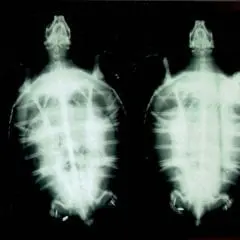

2012- Photo Depictions of Auto-Grafting a Juvenile Green Turtle.